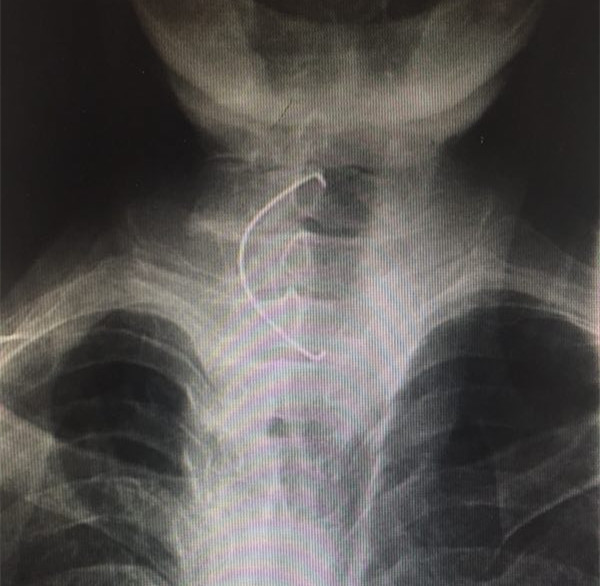

近日,我院耳鼻咽喉头颈外科病院顺利为82岁男性患者取出假牙一枚。

该患者系82岁男性,去年6月份因“误咽假牙”之主诉急诊入院。食道钡透显示“食道上段异物”,在全麻下顺利取出假牙,交给患者家属。该假牙为上颌部全假牙,长约7公分,患者平安出院。近日该患者再次“误咽假牙8小时”急诊入院,经询问才知道,患者去年误咽的假牙回家后仍继续使用,导致假牙再次误咽,经食道钡透证实为“食道上段异物”,全麻下顺利取出,告知患者及其家属,此假牙不合适,不能使用,需重新配假牙。该患者两次手术住院费远远超过配假牙费用,且高龄老人全麻手术有很大风险。